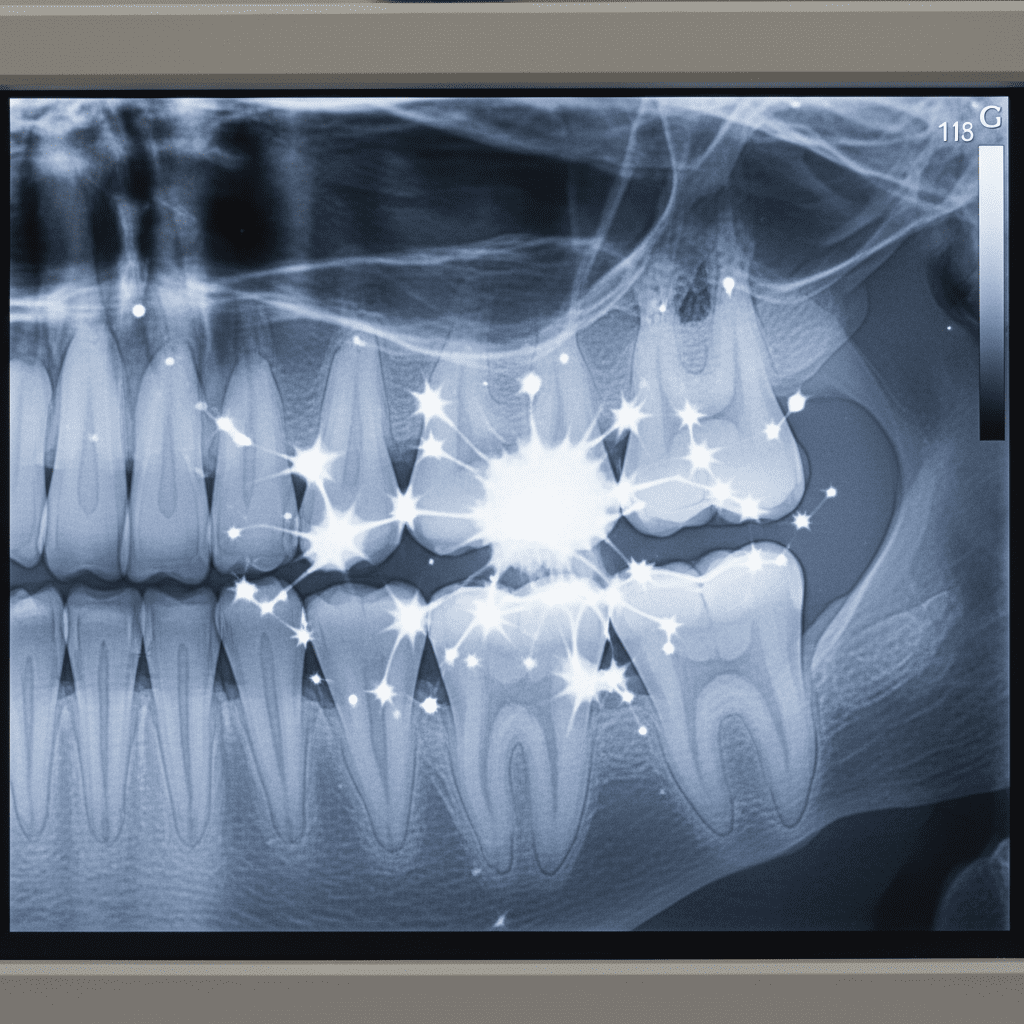

O Twinkle, um artefato observado em radiografias, refere-se ao brilho ou reflexo proveniente de restaurações dentais, especialmente aquelas feitas com materiais altamente reflexivos, como metais. Esse fenômeno é caracterizado pelo seu aspecto cintilante, que pode facilmente ser confundido com outros elementos radiográficos capazes de representar patologias, como cáries ou lesões ósseas.

- Brilho excessivo em áreas específicas da radiografia;

- Contornos nítidos que não correspondem a estruturas dentárias ou ósseas;

- Um padrão que promove confusão com lesões que requerem atenção clínica.

Vários casos na prática clínica ilustram a relevância do reconhecimento do Twinkle. Um caso clássico envolve um paciente que apresentava uma restauração metálica posterior. Durante a análise de sua radiografia periapical, observou-se um brilho intenso, que poderia facilmente ser confundido com uma cárie interproximal. A correta identificação do artefato e a interpretação cuidadosa evitaram que o paciente fosse submetido a tratamentos desnecessários.